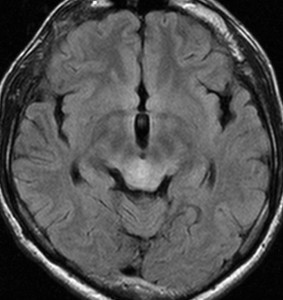

左はT2強調画像,右はFLAIR画像です。中脳視蓋 tectum の中でも上丘が腫瘍化していることが解りますし,松果体は正常の大きさで腫瘍の上に乗っていますから,松果体腫瘍ではないことが解ります。上髄帆にも浸潤しています。